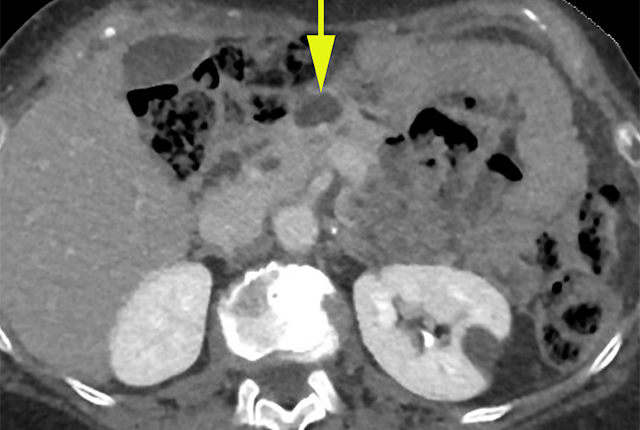

With advances in medical imaging and our aging population, such findings are increasingly common. Doctors call them “incidentalomas.” Although in most cases the attendant risk is low, sometimes they represent very early cancers. Patients can, of course, be consumed with dread at the suggestion of cancer and the financial hit of recommended follow-up scans and biopsies.

The researchers will examine the six most frequently detected incidental lesions: in the lung, liver, kidney, pancreas, adrenal gland, and thyroid gland. They will develop a database of individual records detailing the follow-up costs involved, and ultimate result – a benign or cancerous finding, a “lost” case in which the patient does not return for subsequent care, and whether the incidentaloma resulted in poor health outcomes. Each record would also identify comorbidities and demographic info that might lend insight to risk factors and social determinants of the patient’s long-term health, Gunn said.

“If we look at lung nodules, in the low-risk person with an incidental nodule of less than 6 millimeters, the risk of that being cancer is less than 1%. In that setting we’d only recommend follow-up if the patient has a strong smoking history. At the other end of the spectrum, if the lung nodule is more than 1 centimeter, the cancer risk is substantially higher,” Gunn said. “So we’re hoping to better identify which cases are most appropriate to follow up, and what’s the best way to do that.”